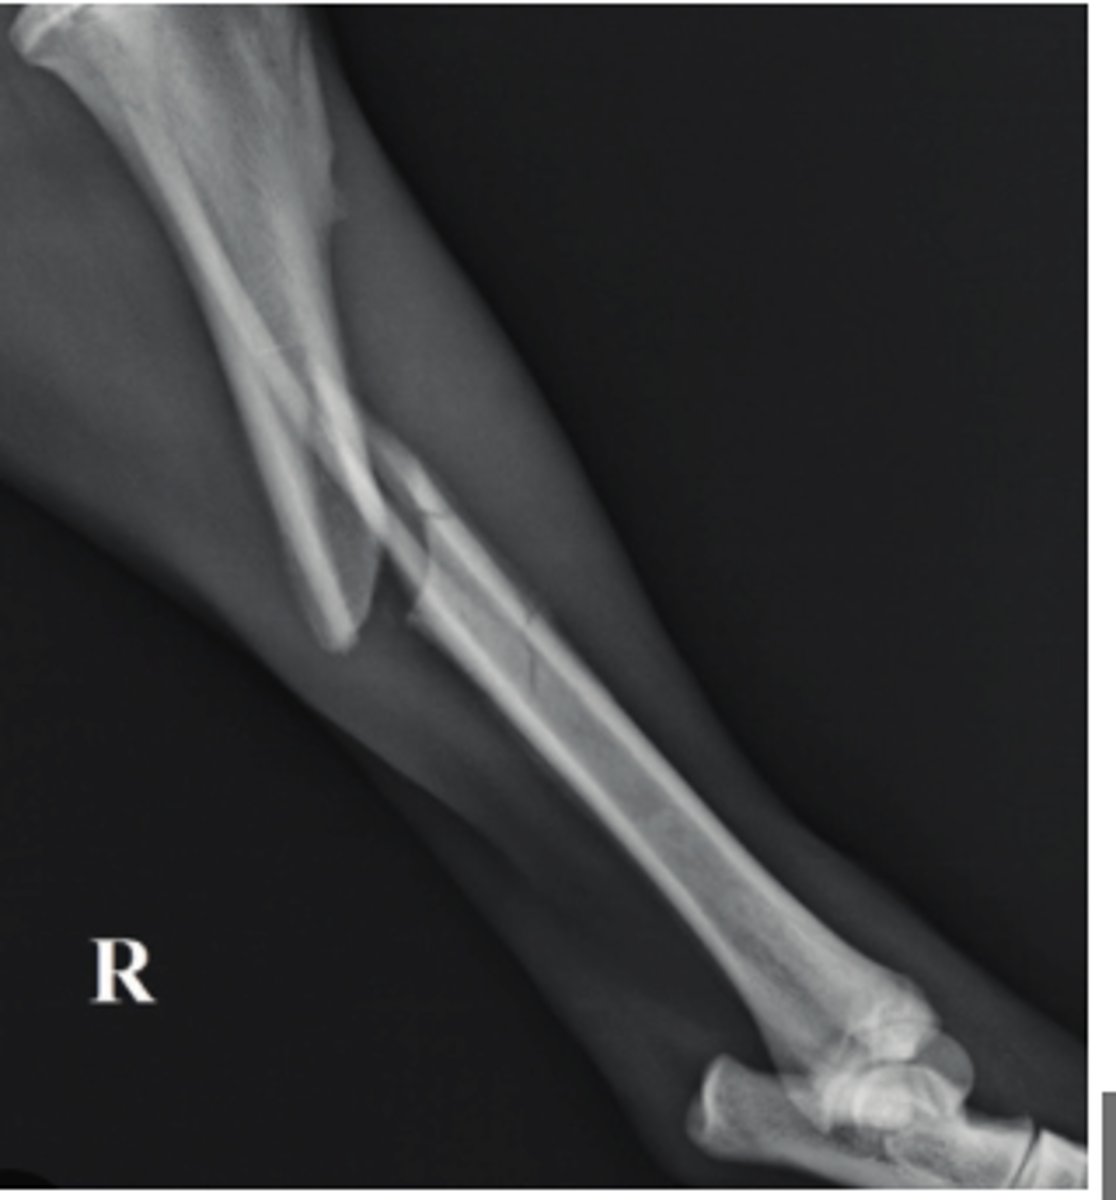

Panosteitis

10 y/o German Shepherd comes in with lameness on the right hind leg; what is the radiographic finding?